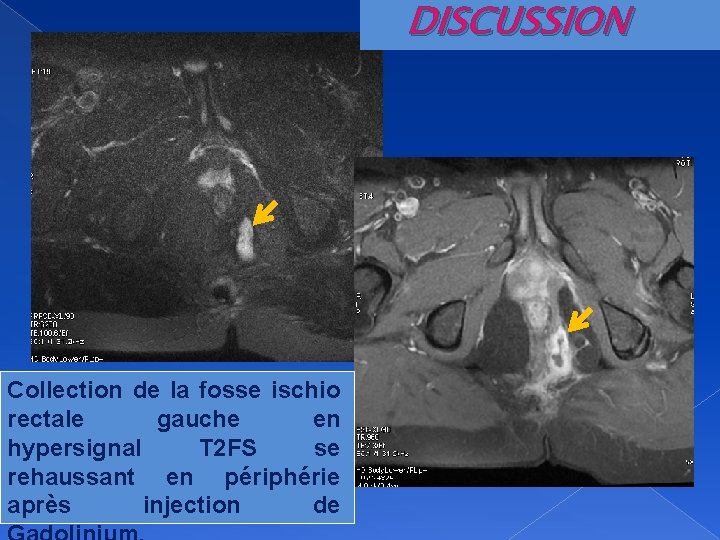

DISCUSSION Collection de la fosse ischio rectale gauche en hypersignal T 2 FS se rehaussant en périphérie après injection de

DISCUSSION Fistule complexe en fer à cheval cravatant la face postérieure du rectum associée à une collection du mésorectum rehaussée en périphérie après injection de Gadolinium. Présence de Seton dans le trajet extraspnictérien droit en hyposignal T 1 et T 2 ( ).